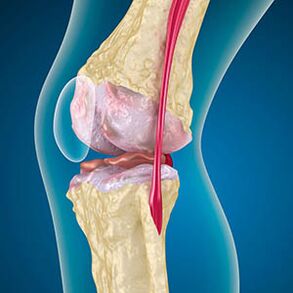

With arthrosis, the cartilage that coating the bone is abrasion or completely absent.Damaged tissue is not a source of pain, as it has no receptors.Inflammation in nearby structures causes characteristic symptoms.

The body continues to regenerate damaged tissues, but the cartilage grows unevenly.As a result, distortions are formed that injure other elements of the joints.The nature of osteophytes is explained by compensation for smooth joint cartilage.Another version shows that the growth of "spurs"It is associated with an attempt to stabilize the joints medically or later as a result of muscle weakness.

In the first stage of arthrosis, which is detected by accident, a slight increase in bone bone occurs.Growth appears in places of the largest instability of the joints.Usually, patients rarely experience pain or discomfort during movement.

The second stage of arthrosis is considered simple.Radiography reveals significant bone spurs, but the cartilage is not affected.The amount of synovial fluid is reduced, but symptoms of pain arise after walking and walking, stiffness in the joints and pain when bending and in the knee position.